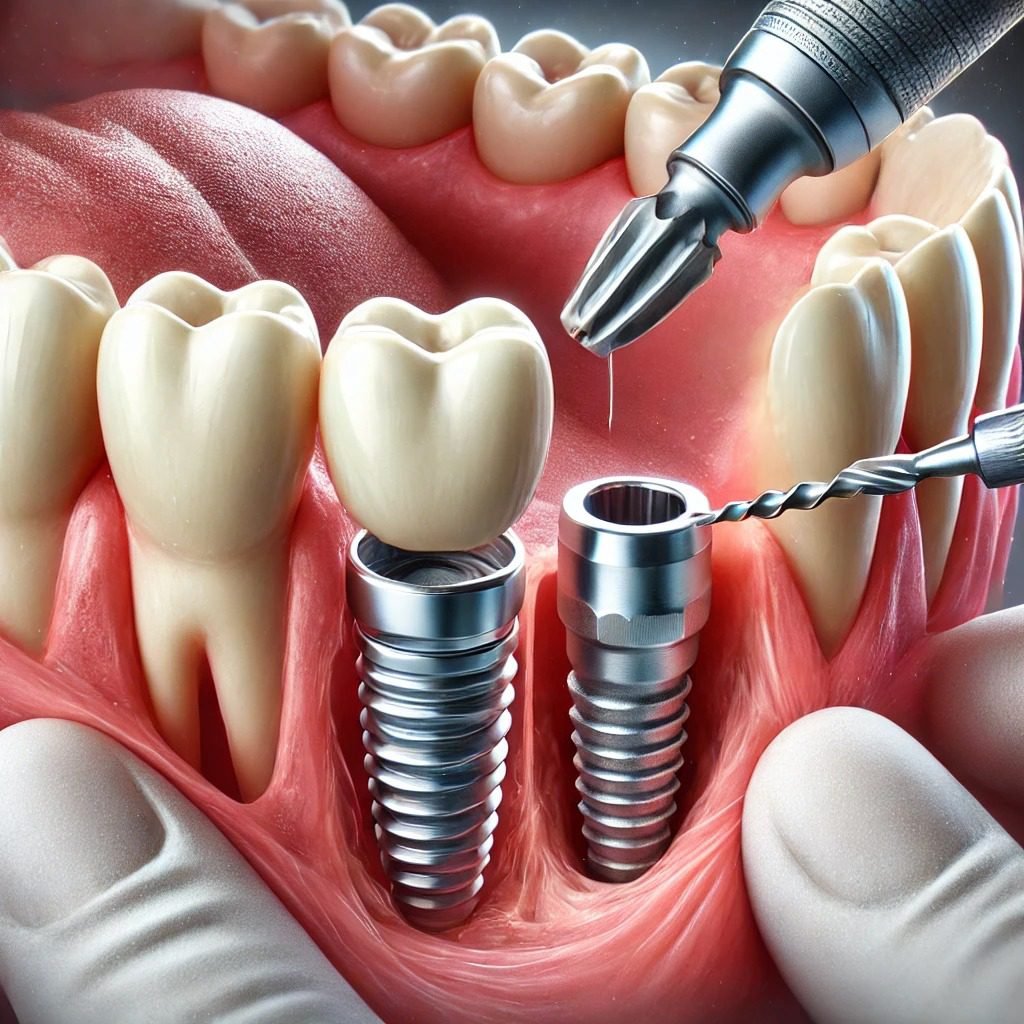

Zahnimplantate

Zahnimplantate

Zahnimplantate bieten eine moderne und effektive Lösung für den Ersatz fehlender Zähne. Hier ein Überblick über die wichtigsten Aspekte: